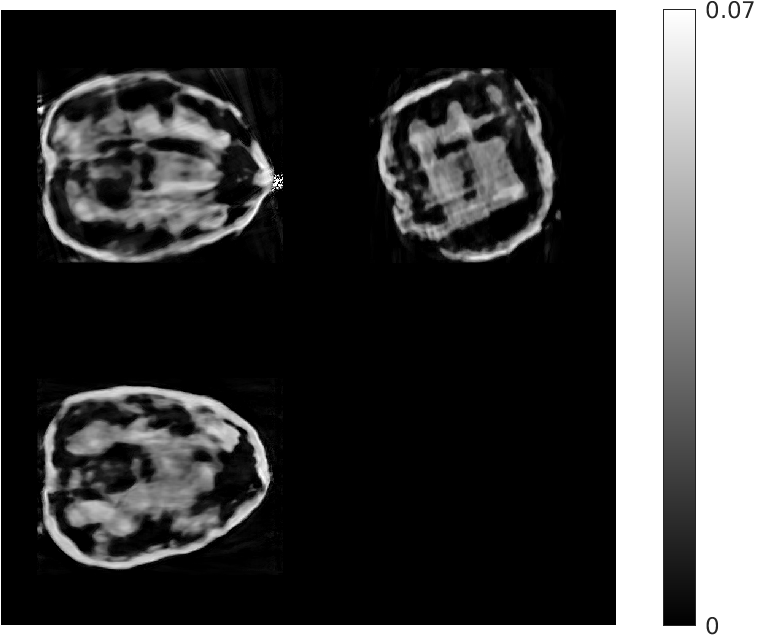

Fig. 4 shows the results of the intermediate steps of the first stage of our reconstruction for walnut 2 (8 views) in the test dataset. While the patch-based destreaking compensates for the blurring introduced by the EP-regularized reconstruction and ‘fills-in’ details in the reconstructed volume, the data-consistency plays a key role in mitigating hallucinations introduced by the CNN, and reinforces image features that are consistent with the acquired measurements.

| Input EP Recon. | Post CNN-based Destreaking | Post Data-consistency |

![]() |

| (NMAE:0.45) | (NMAE:0.38) | (NMAE:0.32) |